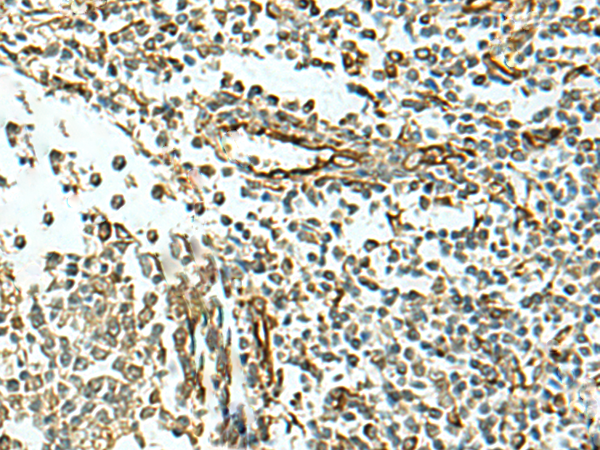

IHC positive control:

Human cervical cancerHuman tonsil

ELISA, IHC